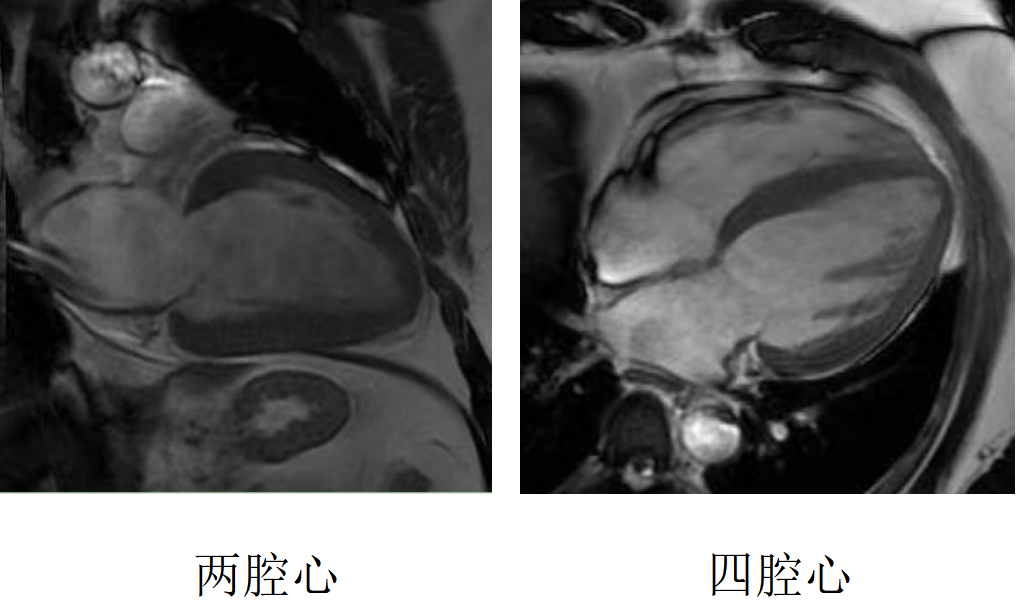

心臟磁共振被稱為心臟“一站式”檢查,通過多參數(shù)成像能夠?qū)π呐K的結構、功能、室壁運動、心臟瓣膜、心肌灌注和活性進行“一站式”評估。主要通過電影序列(短軸、兩腔心、四腔心、三腔心)、T2WI序列、首過灌注序列以及延遲強化序列對心臟進行綜合成像。